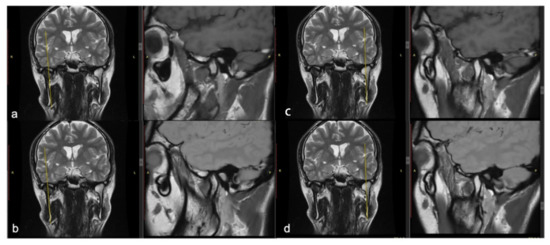

Mandibular Coronoid Process Hypertrophy: Diagnosis and 20-Year Follow-Up with CBCT, MRI and EMG Evaluations

2. Clinical Case